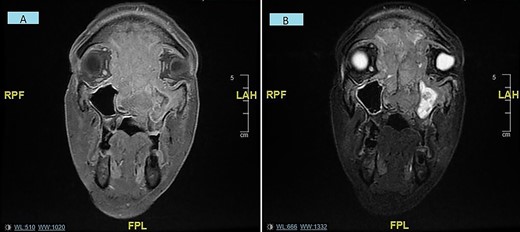

A subsequent magnetic resonance imaging (MRI) was performed within 2 weeks at which point there was complete visual loss. This displayed a large malignant soft tissue mass extending through the nasal cavity with superior intracranial extension plus optic nerve compression and bilateral intra-orbital extension (Fig. 2). A staging CT displayed no DM. An EUA nose plus biopsy was performed, which exhibited extensive invasion in the nasal cavity bilaterally.

(A and B) Coronal MRI sinuses/head images displaying sinonasal mass invading anterior skull base, orbits and intracranially/intradurally (2A—T1 weighted, 2B—STIR).